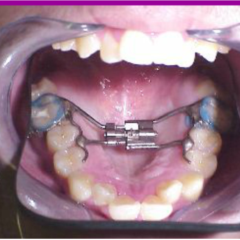

- We are discussing expansion. I am sure, we all have done few. We will revisit protocol.

- There are also other types of expanders besides RPE and we will look intot hem as well.

- Narrow maxilla is indicative of expansion in presense of a crossbite however, expansion is being used as a corrective treatment in Class II and Class III cases as well. We will examine latest literature on the subject.